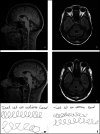

The spectrum of coenzyme Q10 (CoQ10) deficiency syndromes comprises a variety of disorders, including a form of autosomal recessive cerebellar ataxia (ARCA2) caused by mutations in the AarF domain-containing kinase 3 gene (ADCK3). Due to the potential response to CoQ10 supplementation, a timely diagnosis is crucial. Herein, we describe two siblings with a novel homozygous ADCK3 variant and an unusual presentation consisting of isolated writer's cramp with adult-onset. Cerebellar ataxia developed later in the disease course and remained stable during the follow-up. This report highlights that ARCA2 should be considered in the differential diagnosis of familial writer's cramp.